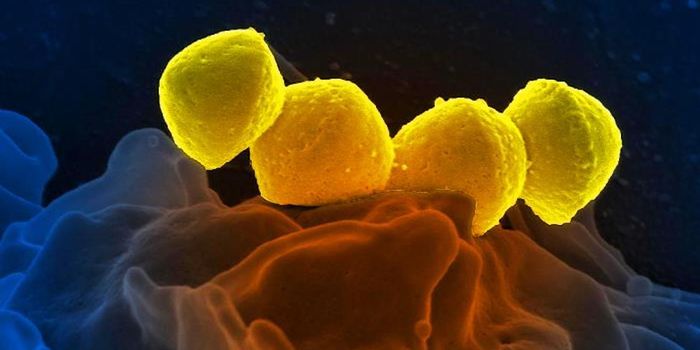

SEP 17, 2021Cell & Molecular BiologyMRSA (methicillin-resistant Staphylococcus aureus) is a well known superbug, a pathogenic microbe that can cause serious ...